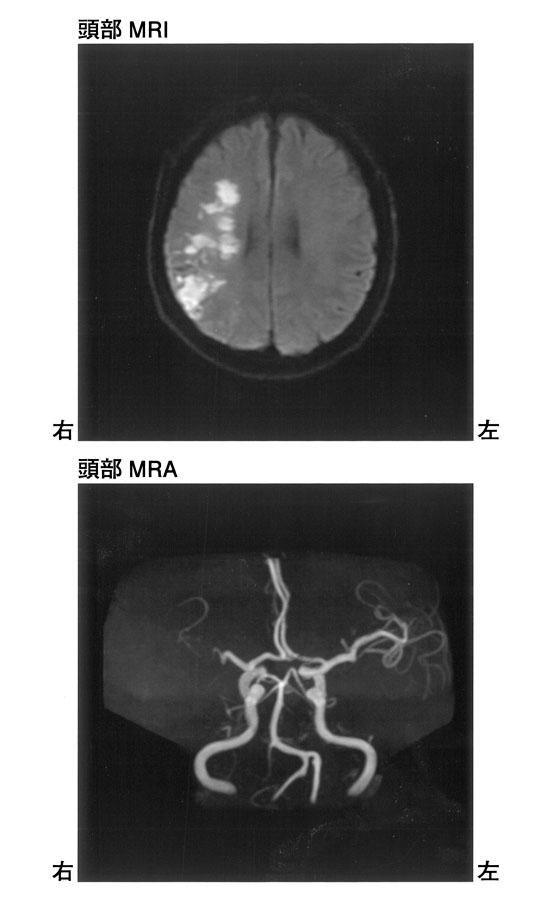

60歳の男性。右利き。歩行困難のため搬送された。発症7日目の頭部MRIと頭部MRAを示す。閉塞している動脈はどれか。

1

右前大脳動脈

2

右中大脳動脈

3

右内頸動脈

4

右椎骨動脈

5

脳底動脈